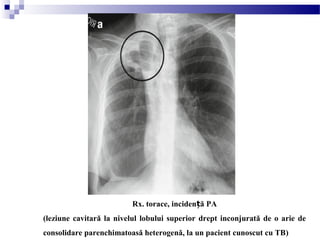

Rx. toracică, inciden ă PAț

Rx. torace, inciden ă PAț

(leziune cavitară la nivelul lobului superior drept inconjurată de o arie de

consolidare parenchimatoasă heterogenă, la un pacient cunoscut cu TB)